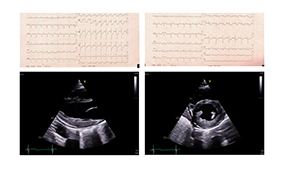

L'électrocardiogramme qualifiant déroule un rythme sinusal régulier avec sus-décalage du segment ST en latéral et en inférieur avec miroir antéro-septal.

L'échocardiographie retrouve une FEVG préservée à 50 % avec une franche hypokinésie de la paroi latérale, inféro-basale et inféromédiane.

L'échocardiographie retrouve une FEVG en amélioration à 50-55 % avec toutefois la persistance d'une hypokinésie latérale et inférieure.

L'électrocardiogramme déroule un rythme sinusal à 71bpm avec un aspect de bloc de branche droit incomplet et une onde Q minime en latéral haut.